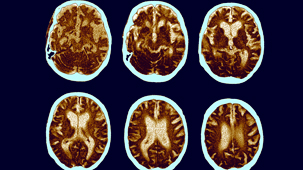

Thanks to the introduction of a range of non-invasive brain imaging techniques, neurosurgical procedures in particular have been revolutionised.

Electroencephalography, Functional Magnetic Resonance Imaging and other machines have increased our knowledge of the brain's inner workings.

Functional Magnetic Resonance Imaging (FMRI) and magnetoencephalography (MEG) have become essential tools for investigating the brain. Thanks to brain scanning, our knowledge of core physical processes - memory, sight, muscle control - has been hugely improved. But are researchers justified in using these tools to delve into more complex and subjective areas such as emotions, aesthetics and morality? (2009)

Dr Mark Lythgoe investigates the technology of brain scanning. Will this technique ever help people suffering from mental illnesses such as depression and schizophrenia? (2007)

Dr Mark Lythgoe, Director of the Centre for Advanced Biomedical Imaging, tells the untold story of medical imaging and why uncovering our inner selves changed the world. (2010)

In the first of a new series of Frontiers, Peter Evans discusses new research into vegetative state. Scientists at Cambridge University recently published a paper suggesting that there were "islands" of brain function in the brain of a patient in a vegetative state. Using Magnetic Resonance Imaging, the researchers have shown that the patient's brain apparently responded to spoken instructions. (2006)

Alzheimer's disease is the most common form of dementia. Damaged tissue builds up in the brain and forms deposits called 'plaques' and 'tangles' which cause the cells around them to die. It also affects chemicals in the brain which transmit messages from one cell to another.

The most common type of dementia occurs when brain tissue degeneration causes a progressive deterioration in mental function and ability. It's more likely to develop as people get older, but can affect younger people too. (2011)